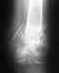

"Посттравматический коксартроз, подвывих головки левой бедренной кости" у больного со спинальной травмой.Что делать?

Молодому человеку врачи поставили диагноз "Посттравматический коксартроз, подвывих головки левой бедренной кости", (Диагноз поставлен в НИИ Травматологии и ортопедии им. Вредена по снимкам). Проблема состоит в том, что у Дениса спинальная травма, и нет чувствительности ниже груди. Основной диагноз: Перелом-вывих Th5 позвонка, компрессионно-оскольчатый перелом Th 6 позвонка. Нижняя параплегия. Ходили на консультацию со снимками к нескольким врачам Санкт-Петербурга. Их ответ звучит примерно так "Случай, который Вы описываете, относится к разряду наиболее сложных и неблагоприятных для оперативного лечения. Причин для этого несколько. Основные - это повышенный риск развития инфекции из-за отсутствия чувствительности и большая частота вывихов после операции, так как мышцы неполноценны и не могут стабилизировать сустав. " Но без этой операции Денис не сможет учится стоять и ходить, реабилитологи и тренера говорят, что, что бы двигаться дальше, обязательно нужно решить вопрос с операцией., т.к он уже достиг максимального результата на своем уровне, теперь нужно начинать реабилитацию в вертикальном положении. На снимках виден небольшой подвывих, но на самом деле бедренная кость часто выскакивает, нога уходит вправо, и нет возможности стоять, даже используя специальные приспособления, также она постоянно выворачивается и право и стала короче... Мы всеми силами пытаемся найти врача, который сможет прооперировать Дениса. Огромными усилиями, мы собираем деньги на его реабилитацию, недавно он прошел операцию по трансплантации стволовых клеток, в г. Новосиборске, и реабилитацию, сейчас в области левого бедра появился большой синяк.... Пытались купить ортрез, что бы фиксировать бедро, но он очень тяжелый и неудобный, заниматься в нем невозможно. Травматологи, к которым мы обращались,боятся делать данную операцию..... Если ее не сделать, то большинство центров отказывается брать Дениса на реабилитацию...Неужели нет никаких шансов, что кто-нибудь согласится сделать данную операцию?Спасибо!